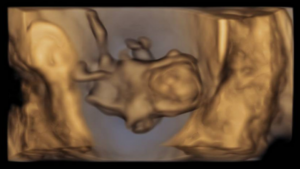

The ultrasound images demonstrated a single spinal column, two stomachs, and two hearts (Figure 2A). Two fused abdomens were observed, along with subcutaneous edema measuring 2.0 mm and 2.1 mm (Figure 2B). In addition, two pairs of moving legs were identified (Figure 2C). The trophoblast was located anteriorly, and a single corpus luteum was observed in the left ovary. Two follow-up examinations were required at 9 and 10 weeks of gestation to establish the diagnosis. At 9 weeks of gestation, the 3D ultrasound images lacked sufficient clarity for a definitive diagnosis (Figure 3). At 10 weeks of gestation, color Doppler imaging demonstrated two distinct cardiac activities, indicating the presence of two separate circulatory systems (Figure 4A). Three-dimensional imaging further revealed the face of one of the conjoined twins and confirmed the presence of two umbilical cords (Figure 4B).